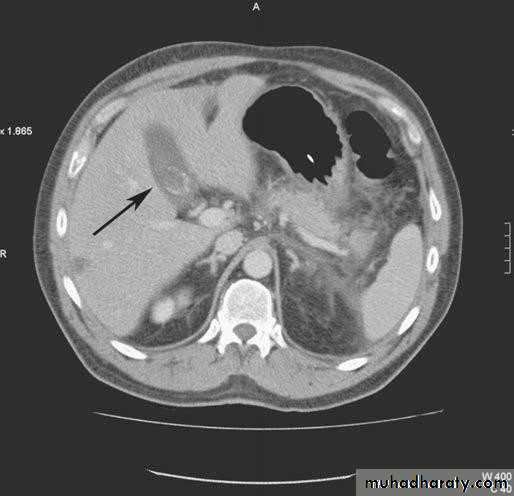

•  Computerized Tomography scan;

•  limited usefulness in investigating the biliary tree

•  Only when there is a possibility of cancer of gall bladder or bile ducts

•  Use of CT scan is an integral part of the differential

• diagnosis of obstructive jaundice

• CT SCAN

• Computed tomography scan demonstrating a gallstone

• within the gall bladder (arrowed).